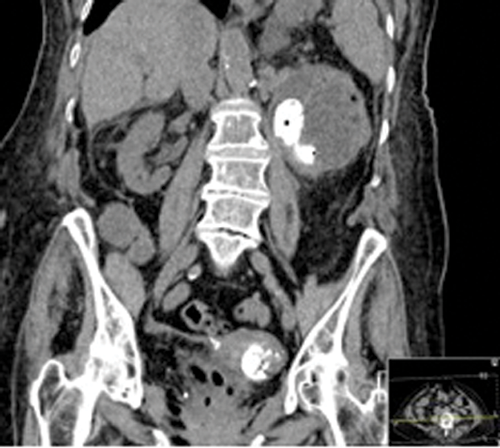

Figures 1: Patient A. Air in the collecting system extending into renal parenchyma.